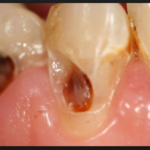

Кариес корня зуба фото

Кариес на корне зуба визуально практически никогда не определяется. Очень редко, и лишь в случаях, когда зубной камень значительно опустил ткани десны, может быть видно темное пятно или изъязвленный участок эмали. Чаще всего кариесом развивается на корнях передних нижних зубов и в межзубном промежутке. Во втором случае можно заметить снижение высоты десневого сосочка и увеличение межзубного промежутка в самой нижней его части.

Наиболее вероятным осложнением является разрушение корневой части зуба и необходимость в его удалении, даже если коронковая часть абсолютно цела и здорова. Кроме этого, если на корне зуба кариес, это ставит под удар опорно-связочный аппарат, который может быть инфицирован кариес-образующими бактериями. Как результат, развивается периодонтит, периостит, периодонтальные осложнения (абсцесс, флегмона), киста корня и другие осложнения. Ни одно из них не проходит без последствий как для зубочелюстной системы, так и для организма в целом.